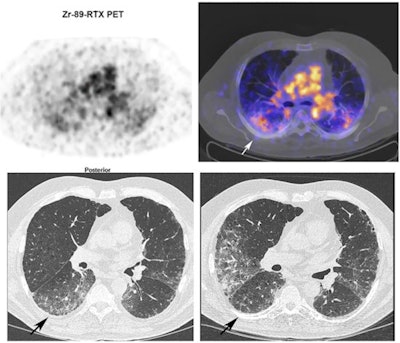

Zr-89 rituximab is a PET radiotracer designed to bind to CD20 receptors on the B cells and thus can reveal varying levels of these "target" cells on PET scans. In a previous study, the authors demonstrated the safety of the approach. This study was conducted to further evaluate it in a group of prospective patients.

The researchers recruited 21 patients with IMID-IP with deteriorated pulmonary function. Patients had not been treated with immunotherapy previously and received a dose of 1,000 milligrams rituximab on day one. PET/CT was performed on days three and six, with levels of radiotracer uptake (standard uptake values, SUV) by B cells calculated for each patient.

Then, prior to and six months after treatment, the researchers compared the radiotracer uptake with pulmonary function tests (PFT) such as forced vital capacity (FVC), which were used to classify patients as reponders or nonresponders.

Fifteen patients (71%) were classified as responders. Pulmonary Zr-89 rituximab PET SUVmean was significantly correlated with change in patient FVC (K = 0.49) when using target-to-background ratios, but not when using SUVmean alone, the researchers found. In addition, Zr-89 rituximab SUVmean was significantly higher in responders than in nonresponders, according to the findings.